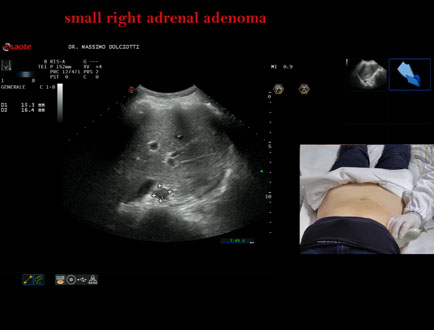

Data inserimento: 06/11/2025

Ecografia del: 31/10/2025

Strumento: Esaote MyLab Eight

Sonda: Convex Multifrequenza 1-8 MHz

Età Paziente: F 69 anni

Motivazione dell'esame: follow up per piccolo adenoma surrenalico.

Commento all'esame: le immagini ed il video documentano in sede surrenalica destra, formazione ipoecogena, a margini definiti, rotondeggiante, delle dimensioni di 15,8 x 14,8 mm, da ricondurre ad adenoma surrenalico.

Conclusioni: piccolo adenoma surrenalico destro (small right adrenal adenoma).

Presentazione: Dr. Massimo Dolciotti - Ancona

Elaborazione digitale: Andrea Dini - Ancona